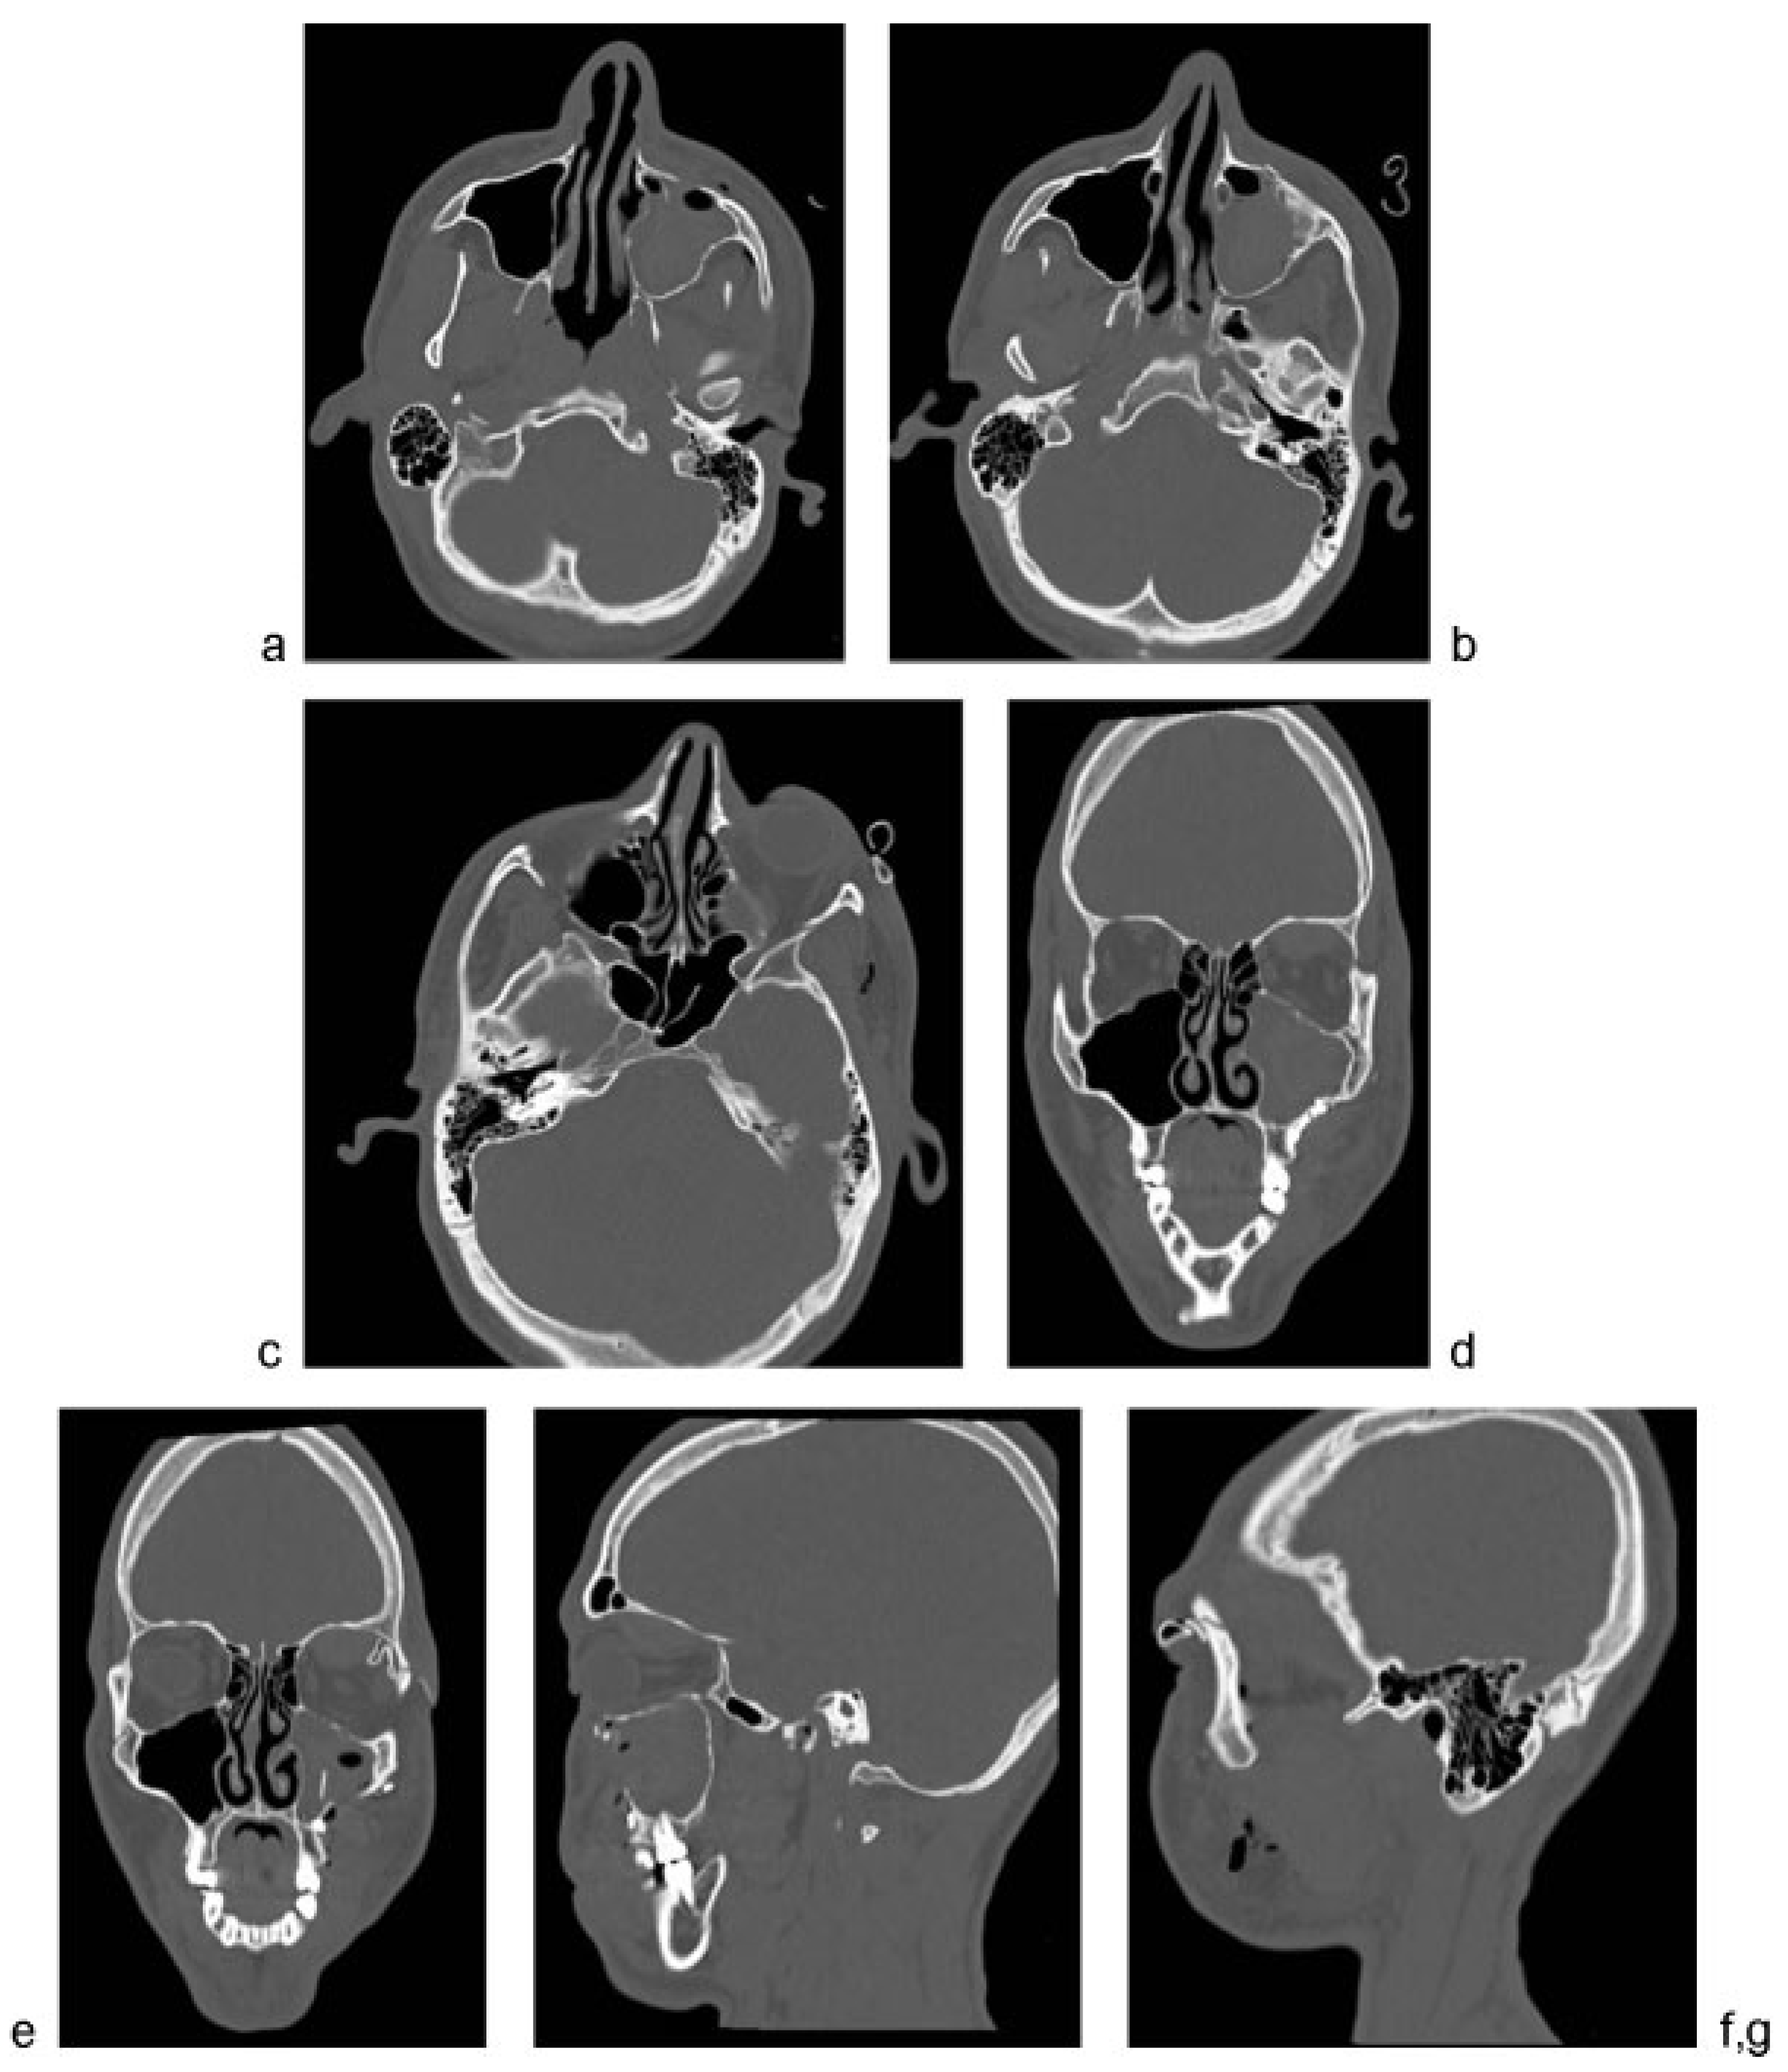

Maxillofacial computed tomography demonstrated a displaced, nonrotated left OZMC fracture (Figure 2). There was no evidence of extraocular muscle entrapment, large orbital floor defect, retrobulbar, or intraorbital hematoma. Routine preoperative laboratory evaluation, including coagulation studies, was unremarkable.

Figure 2. Preoperative maxillofacial computed tomography demonstrated a depressed, nonrotated Orbitozygomaticomaxillary Complex fracture. There is significant (a,b) posterior displacement of the zygomatic body, (c) with minimal displacement of the zygomatic arch, (d) medial displacement of the sphenozygomatic suture, and (e) mild displacement at the frontozygomatic suture. (fj) The orbital floor was not significantly displaced. (d,f,i,j) No retrobulbar or intraorbital hematoma was noted preoperatively.